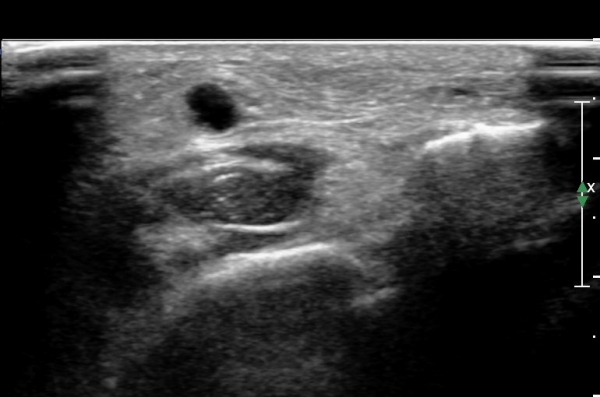

¾ÕÂÊ ¸»´Ü °æ°ñºñ°ñ°üÀý ¾à 5cm ±ÙÀ§ºÎ Ⱦ´Ü몀°Ë»ç ½Ã õºñ°ñ½Å°æ Àü¸é¿¡ Àú¿¡ÄÚ ³¶Á¾¿¡ ÀÇÇÑ ½Å°æ ¾Ð¹ÚÀÌ °üÂûµÈ´Ù(ÀÌ °üÂûµÈ´Ù(»çÁø 6, 7).

¸»´ÜÀ¸·Î °¥ ¼ö ·Ï ³¶Á¾ÀÌ Ä¿Áø°í õºñ°ñ½Å°æ ¾Ð¹ÚÀº ½ÉÇØÁø´Ù(»çÁø 8).

³¶Á¾À» Á¾´Ü¸éÀ¸·Î °üÂûÇÏ´Ï ³¶Á¾ÀÌ ¸»´Ü °æ°ñºñ°ñ°üÀý¿¡¼ À¯·¡µÊÀÌ È®ÀεȴÙ(»çÁø 9).